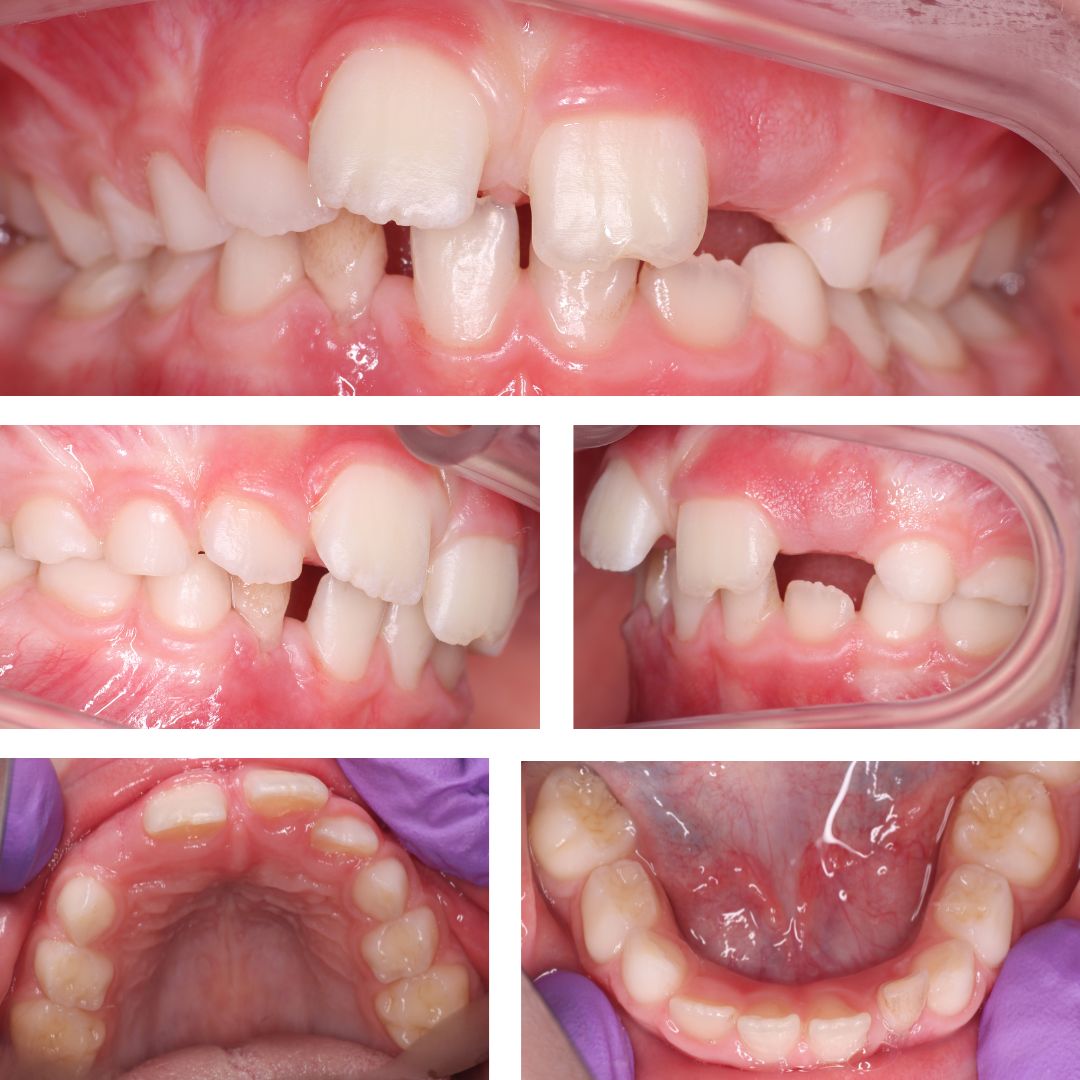

Обращение в клинику связано с жалобой на неровное положение центральных резцов, при этом проблем с прикусом не выявлено.

После диагностического обследования было предложено исправить положение зубов на детских элайнерах Kinder Smile.

Посмотрите фото ДО и ПОСЛЕ. Как вам такое 🔥 преображение?